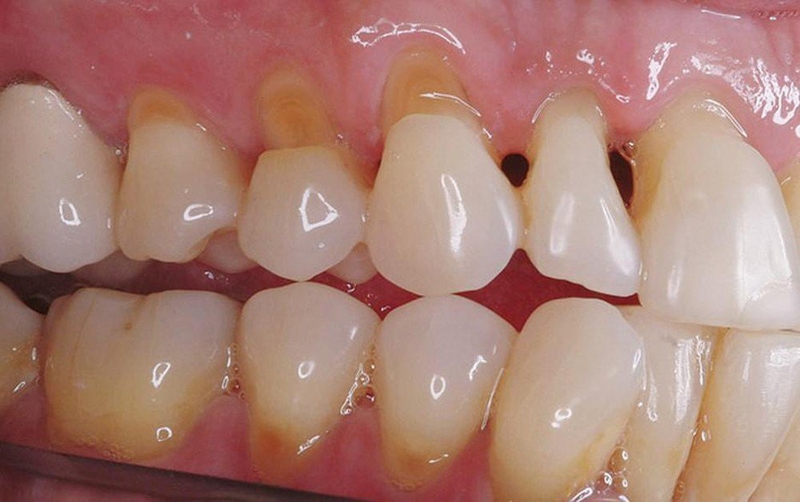

Mòn cổ chân răng là hiện tượng men răng ở vùng cổ chân răng bị mòn khuyết vào trong. Biểu hiện của tình trạng này là khi ăn uống hoặc hít không khí lạnh thì răng sẽ có cảm giác bị ê buốt. Đồng thời trên răng bị ăn mòn sẽ xuất hiện vết mòn hình chữ V.

Chân răng bị mòn là hiện tượng men răng ở vùng cổ chân răng bị mòn khuyết vào trongTheo các chuyên gia nha khoa thì bệnh chân răng bị mòn chủ yếu xảy ra bởi các nguyên nhân sau đây: